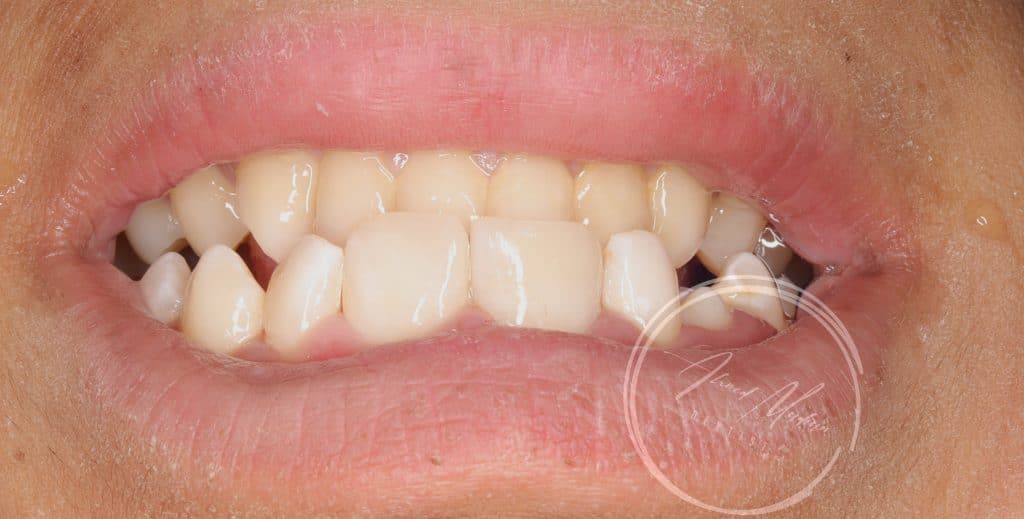

14 y male patient came to the office complaining of trauma in the anterior region

Tooth no 11 showed complicated crown root fracture , exposed pulp , closed apex

Tooth no 12 uncomplicated corwn fracture , class lV

21 22 are intact